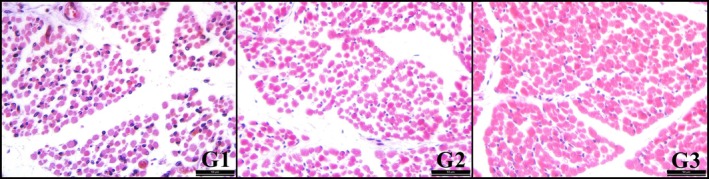

This study evaluated the effects of subclinical pregnancy toxaemia (SPT) on fetal skeletal muscle development and assessed the potential protective role of L-carnitine supplementation during gestation. A total of 18 crossbred Hamdani ewes underwent oestrous synchronisation, natural mating and pregnancy confirmation via ultrasonography on day 45 post-mating. The ewes were managed according to NRC (2007) dietary guidelines until day 100 of gestation, after which they were assigned to three experimental groups: subclinical PT group (group 1; G1, n = 6), treatment group (subclinical PT + L-carnitine, group 2; G2, n = 6) and control group (group 3; G3, n = 6). Blood β-hydroxybutyrate (βHBA) concentrations were measured on day 100 and 138 of the gestation. Then, all ewes were slaughtered for fetal muscle sampling from the Musculus Longissimus Dorsi (MLD) and Vastus Lateralis (VL). Results indicated a significant reduction in muscle fibre number and fibre diameter in both MLD and VL in the SPT group (G1) compared to the control (G3) (p < 0.05). No significant differences were observed between G1 and G2 or between G2 and G3 for these parameters (p > 0.05). On the other hand, large effect sizes for group and pairwise comparisons imply that SPT may negatively affect prenatal muscle development and L-carnitine supports muscle development during the prepartum period. These findings highlight the negative effects of SPT and protective effects of L-carnitine supplementation on fetal skeletal muscle development in ewes with SPT. The observed deficits may negatively impact postnatal growth, survival rates and meat quality. Further investigations are warranted to optimise maternal nutrition strategies and evaluate therapeutic interventions aimed at mitigating the adverse impacts of SPT on fetal muscle development in ruminants. Furthermore, L-carnitine supplementation may be a useful in compensating for the negative effects of SPT.